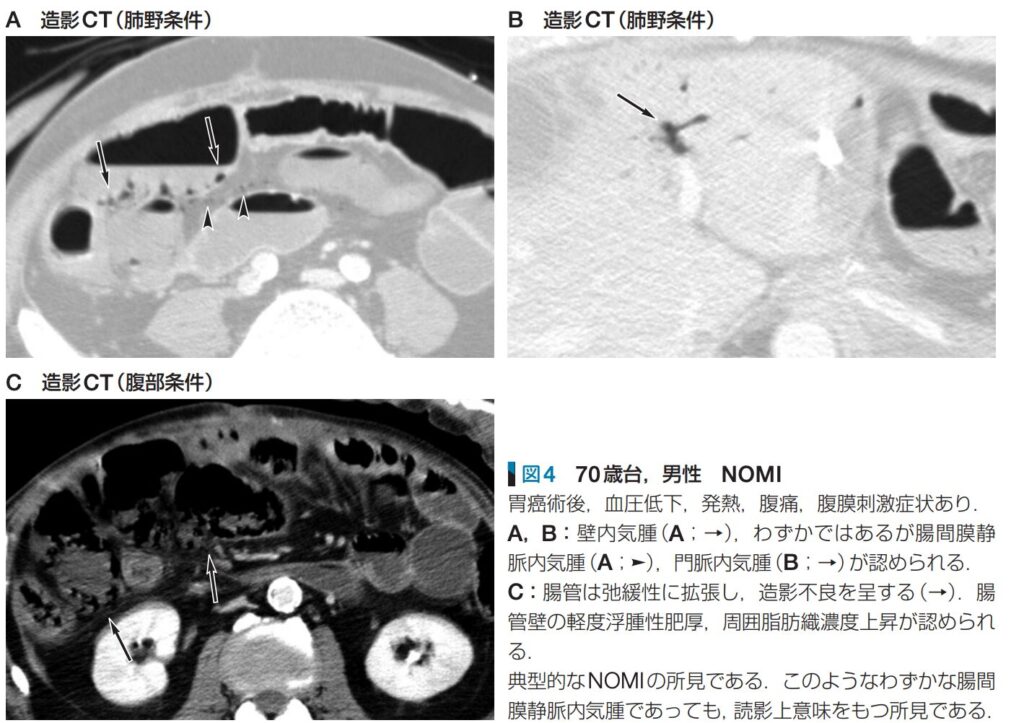

- 腸管気腫症(壁内ガス): 39%(41例)に認められます。粘膜の壊死によって壁内にガスが漏れ出ている状態を反映しています。

- 門脈内ガス: 22%(23例)に認められます。腸管気腫症のガスが腸間膜静脈から門脈系へと進行したことを示します。

1. 腸管壁の厚さを観察する(肥厚や菲薄化)

- 腸管壁は浮腫性の肥厚を示すことが多いですが、壊死が進行すると紙のように菲薄化している場合もあります。

2. 腸管壁の状態を観察する(壁内ガス・造影効果の欠如)

- 腸管壊死を示唆する重要な所見として、造影効果の欠如(壁の造影不良)や腸管壁内ガス(腸管気腫症)がないかを確認します。また、単純CTで壁が高吸収(壁内血腫)を示していないかも確認します。

3. 周囲の変化に注目する(血管内ガス・脂肪織の吸収値上昇)

- 腸管壊死を示唆するさらに重篤なサインとして、腸間膜静脈内や門脈内のガスがないかを探します。また、周囲の腸間膜脂肪織の吸収値が上昇していないかにも注目します。